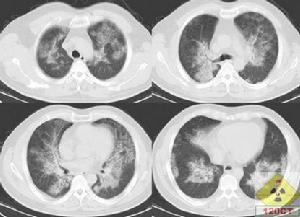

典型的胸片表現是雙肺對稱的肺泡填充性陰影,肺門旁的浸潤陰影延伸至外帶,呈“蝴蝶狀”分布,雙肋膈角往往不受累及。可是多數的PAP病例報導PAP的胸片沒有上述典型的特徵,因此X線胸片的表現通常不具有特異性。胸部HRCT能清晰地顯示肺部受累的範圍和特點。磨玻璃影與正常肺臟分界明顯,呈“地圖”樣分布;小葉內和小葉間隔增厚,呈多角形,稱為“鋪路石征”;或者表現為大片的實變影伴支氣管充氣征,周圍環繞著磨玻璃影。極少數病例有肺間質纖維化的表現,往往是疾病晚期。這些病變的程度和範圍與肺功能以及肺臟氣體交換障礙密切相關。